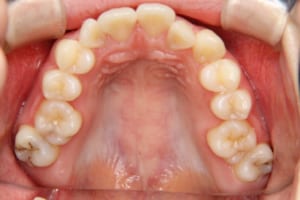

治療前

その他/備考 上顎右側中切歯および側切歯が、埋伏していた犬歯によって歯根吸収していました。

牽引に半年かかりました。